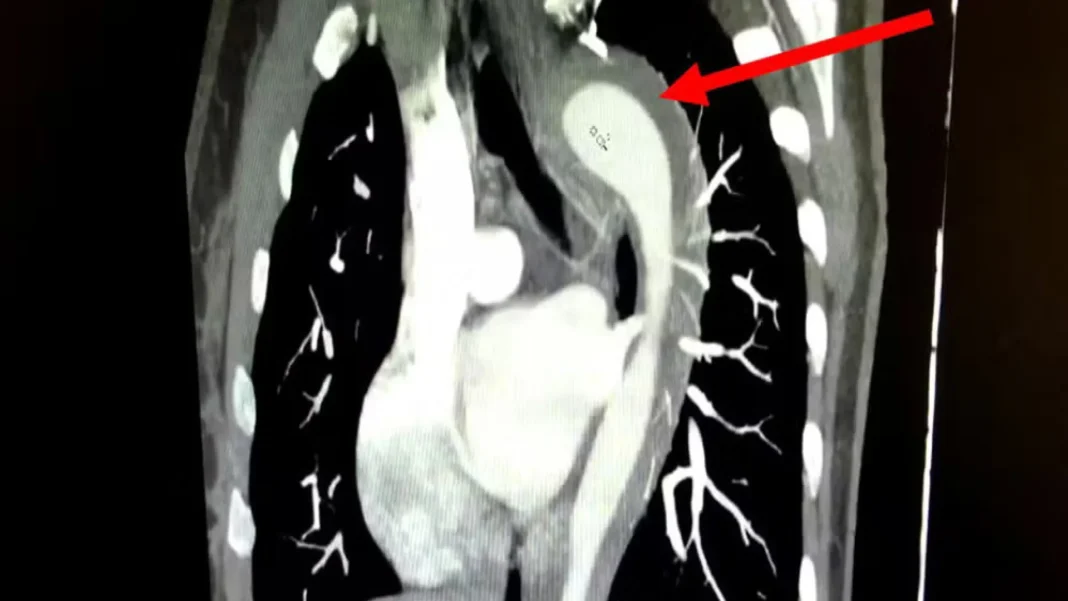

Mulher de 45 anos rompe aorta durante orgasmo e passa por cirurgia clicknoroeste.com 12 de julho de 2025 FacebookTwitterPinterestWhatsApp Um caso raro e de alto risco envolvendo a ruptura da aorta foi relatado pelo American Journal of Case Reports. A paciente, uma mulher de 45 anos, d… leia mais no Notícias ao Minuto Brasil aqui. VEJA TAMBÉM Vintage Culture e Maz farão abertura de show de Shakira, no Rio Preço do petróleo sobe mais de 6% e é o maior em três semanas após novas ameaças de Trump Sargento do Exército é preso sob suspeita de atropelar mulher no Distrito Federal Palmeiras quer sair da Libra e é contra acordo com Flamengo Eu sou musicalmente preguiçoso, comenta Gilberto Gil ao analisar sua carreira Vintage Culture e Maz farão abertura de show de Shakira, no Rio 29 de abril de 2026 Preço do petróleo sobe mais de 6% e é o maior em três semanas após novas ameaças de Trump 29 de abril de 2026 Sargento do Exército é preso sob suspeita de atropelar mulher no Distrito Federal 29 de abril de 2026 Vintage Culture e Maz farão abertura de show de Shakira, no Rio 29 de abril de 2026 Preço do petróleo sobe mais de 6% e é o maior em três semanas após novas ameaças de Trump 29 de abril de 2026 Sargento do Exército é preso sob suspeita de atropelar mulher no Distrito Federal 29 de abril de 2026 Palmeiras quer sair da Libra e é contra acordo com Flamengo 29 de abril de 2026 Vintage Culture e Maz farão abertura de show de Shakira, no Rio Preço do petróleo sobe mais de 6% e é o maior em três semanas após novas ameaças de Trump Sargento do Exército é preso sob suspeita de atropelar mulher no Distrito Federal Palmeiras quer sair da Libra e é contra acordo com Flamengo Eu sou musicalmente preguiçoso, comenta Gilberto Gil ao analisar sua carreira Banco Central reduz juros básicos para 14,5% ao ano Jorge Messias é rejeitado para vaga de ministro do STF Ex-Tiazinha diz que se sentiu traída com chegada da Feiticeira Com um pênalti para cada lado, Atlético e Arsenal empatam em primeiro duelo Messias diz que não tinha relação direta com Lula e nunca foi filiado ao PT Governo contraria Meta e mantém WhatsApp restrito a menores de 14 anos Juliana Paiva anuncia noivado com Danilo Partezani